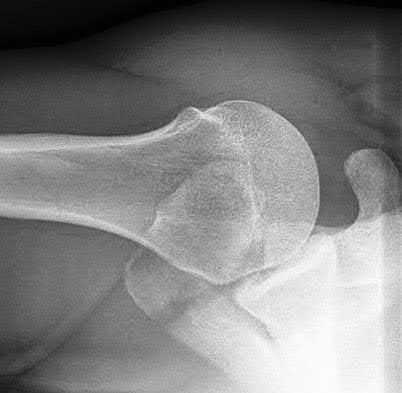

Figure A is an AP radiograph of a posterior knee dislocation. Figure B is a lateral showing the same injury.